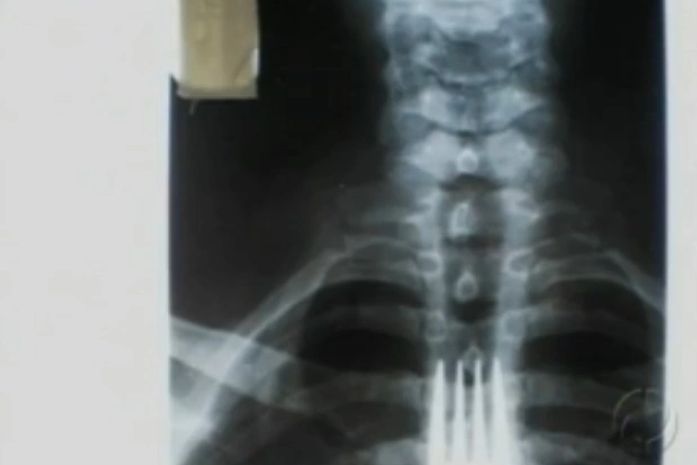

Um paranaense de Bandeirantes, no norte do Paraná, engoliu um garfo durante uma refeição por volta das 15h de quinta-feira (16). A cirurgia para retirada do objeto do esôfago foi realizada com sucesso na Santa Casa, na manhã de sexta-feira (18). O homem, de 50 anos, passa bem e está em observação na unidade semi-intensiva do hospital.